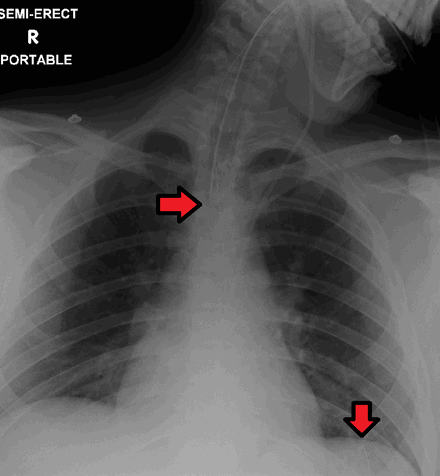

Эндотрахеальная трубка и назогастральный зонд , как видно на рентгенограмме. Оба в хорошем положении.

Следует проявлять особую осторожность, чтобы трубка не прошла через гортань в трахею и вниз в бронхи. Надежный метод - забрать немного жидкости из трубки с помощью шприца . Затем эту жидкость проверяют с помощью pH-бумаги (не лакмусовой бумаги ) для определения кислотности жидкости. Если pH равен 4 или ниже, пробирка находится в правильном положении. Если это невозможно, правильное положение трубки подтверждается с помощью рентгеновского снимка грудной клетки / брюшной полости. Это самый надежный способ обеспечить правильное размещение трубки NG. Использование рентгеновского снимка грудной клетки для подтверждения положения является ожидаемым стандартом в Великобритании с проверкой и подтверждением доктором / врачом. Будущие методы могут включать измерение концентрации ферментов, таких как трипсин, пепсин и билирубин, для подтверждения правильного размещения пробирки NG. Поскольку ферментное тестирование становится все более практичным, позволяя проводить измерения быстро и дешево у постели больного, этот метод можно использовать в сочетании с тестированием pH в качестве эффективной и менее вредной замены рентгеновского подтверждения. Если трубка должна оставаться на месте, рекомендуется проверять положение трубки перед каждым кормлением и не реже одного раза в день.